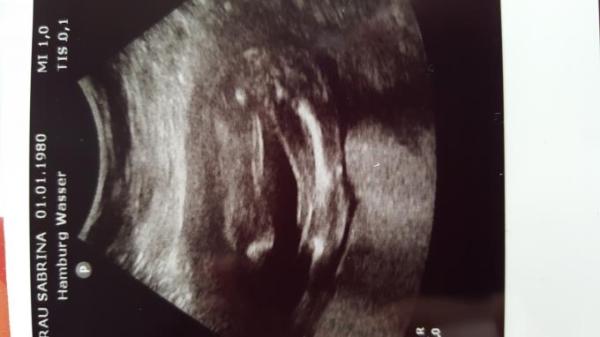

So mein Betriebsarzt hat das Bild gemacht und sagt was anderes wie meine Kollegen

Ich würde sagen Mädchen :-)

Ich würde auch auf ein Mädchen tippen.

Das meine der Betriebsarzt auch, aber sicher ist er sich auch nicht. Meine Kollegen wollen da angeblich etwas männliches gesehen haben Also ich sag auch Tendenz Team Rosa :D

Bin ganz schlecht darin... Meine aber, einen Pipimanm zu sehen....

Ich finde es sieht nach Mädchen aus.

Ich hätte jetzt doch auf Jungen getippt! Sind dass nicht zwei kleine Eier da vor den Beinen? Den Schnippel sieht man wenn nur sehr verschwommen dazwischen!? Aber keine Ahnung!

also habe einen vergleich 23 woche von meiner kleinen gleiche position und deshalb sage ich jungen schamlippen sehen anders aus nämlich wie eine kaffeebohne und das sieht sehr nach schnippel aus

Also ich sehe auch einen kleinen Pipi. Bei meiner kleinen sieht man die Schamlippen nämlich wirklich wie eine Trennung einer Kaffeebohne. Egal was es wird Hauptsache gesund:-) Lg